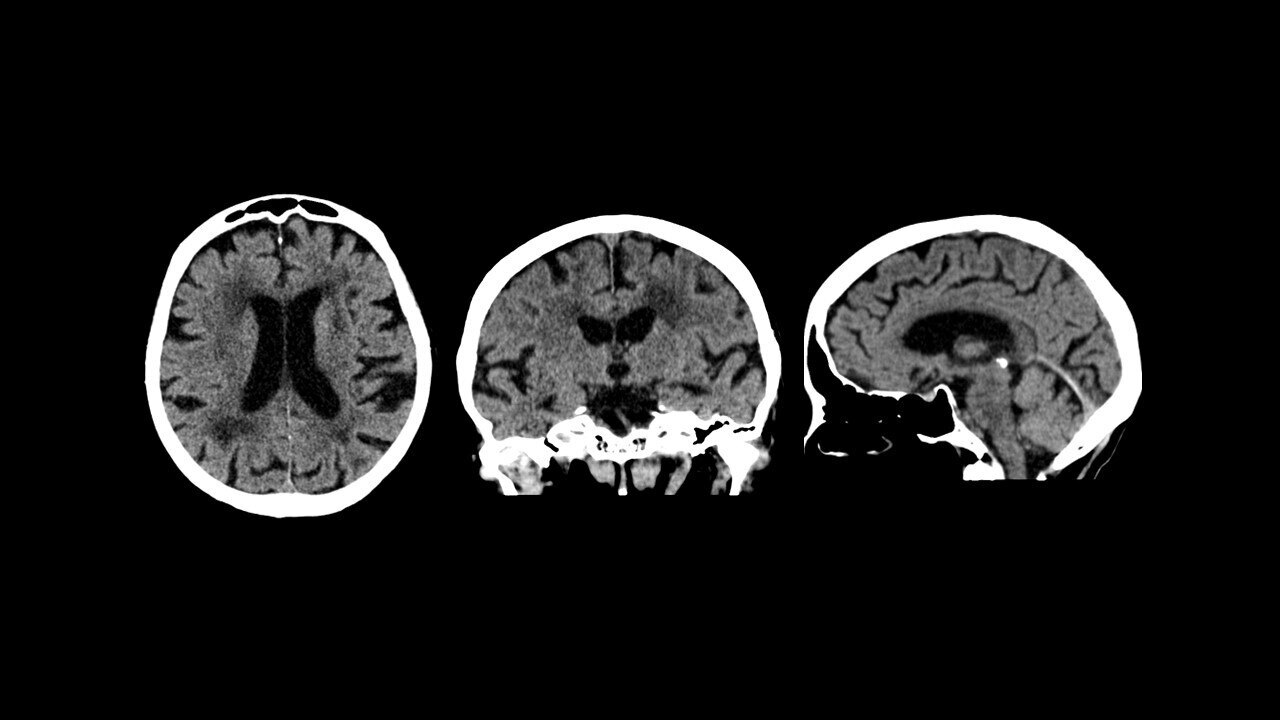

veeva img